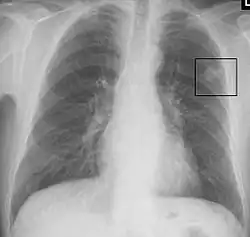

Le cancer du poumon peut être vu sur les radiographies thoraciques et le scanner. Le diagnostic est confirmé par une biopsie. Ceci se fait généralement par bronchoscopie, ou par biopsie guidée par scanner. Le traitement et le pronostic dépendent du type histologique du cancer, de son stade (degré de dissémination), et de l'état général de santé du patient.

Diagnostic

il n'existe pas de règle précise déclenchant les explorations à partir des premiers symptômes, le plus souvent peu expressifs[127],[3]. Mais dans tous les cas, lorsque le cancer est suspecté, le diagnostic doit déboucher sur une preuve histologique, et sur la délimitation de son extension.

Beaucoup des symptômes du cancer du poumon (douleurs osseuses, fièvre et perte de poids) sont non spécifiques ; chez les patients âgés, ils peuvent être attribués à une comorbidité[4]. Chez beaucoup de patients, le cancer s'est déjà étendu au-delà du site original au moment où le patient ressent les premiers symptômes et consulte. Des sites fréquents de métastases sont le cerveau, les os, les glandes surrénales, le poumon controlatéral (de l'autre côté), le foie, le péricarde et les reins[133]. Environ 10 % de tous les patients atteints par le cancer du poumon n'ont pas de symptôme diagnostic ; ces cancers sont découverts par hasard à la suite d'une radiographie de la poitrine[3].

La radiographie thoracique est la première mesure à prendre si un patient se plaint de symptômes pouvant suggérer un cancer du poumon. Ceci peut révéler une masse évidente, un élargissement du médiastin (qui suggère une extension aux ganglions lymphatiques qui s'y trouvent), une atélectasie (affaissement), une inflammation (pneumonie) ou un épanchement pleural. En l'absence de signes radiographiques, mais si les soupçons sont élevés (par exemple, un gros fumeur avec hémoptysie), une bronchoscopie ou un scanner peuvent donner l'information nécessaire. La bronchoscopie ou la biopsie guidée par scanner sont souvent utilisées pour identifier le type de tumeur[3].

Le diagnostic différentiel pour les patients qui présentent des anomalies de la radiographie thoracique consiste à distinguer le cancer du poumon des maladies non malignes. Ces dernières peuvent être des infections, telles que la tuberculose ou la pneumonie, ou des inflammations comme la sarcoïdose. Ces maladies peuvent donner lieu à des lymphadénopathies du médiastin, ou à des nodules du poumon, qui peuvent imiter des cancers du poumon[4]. Le cancer du poumon peut par contre être une trouvaille incidentelle : un nodule pulmonaire solitaire (lésion en « pièce de monnaie ») vu sur une radiographie du thorax ou un scanner pris pour une tout autre raison.

Le poumon est un endroit fréquent pour le développement de métastases de tumeurs développées initialement aux dépens d'autres organes. Ces cancers secondaires sont identifiés par l'organe d'origine ; ainsi, une métastase de cancer du sein dans le poumon est encore reconnue comme cancer du sein. Ils ont souvent une apparence ronde caractéristique à la radiographie[145]. Chez les enfants, la majorité des cancers du poumon sont secondaires[144].